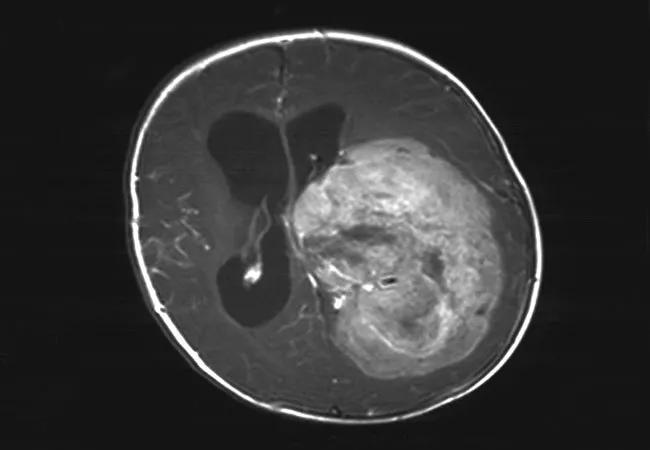

The rare, highly invasive pediatric brain tumors known as choroid plexus carcinomas (CPCs; Figure 1) are often associated with Li-Fraumeni syndrome (LFS). This hereditary disorder, usually characterized by an underlying germline mutation of the TP53 tumor suppressor gene, predisposes carriers to sarcomas and malignancies of the brain, breast and adrenal glands.

Figure 1. T1-weighted MRI with contrast showing a choroid plexus carcinoma.